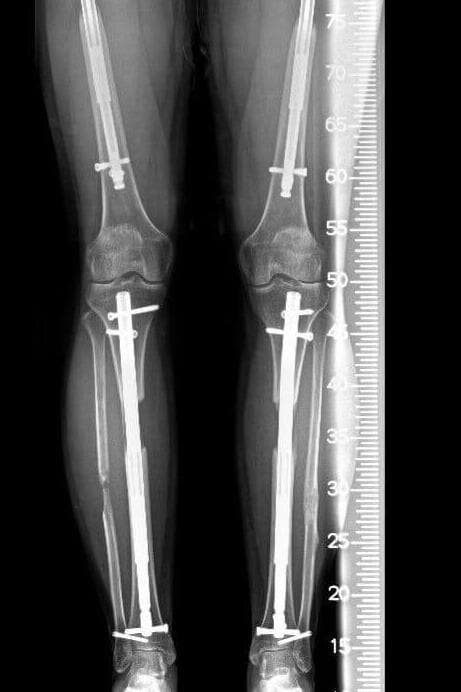

לפני כשנה וחצי עבר עומר את הניתוח, שכלל הארכה כפולה בו זמנית של כל ארבע עצמות הרגליים - שתי עצמות השוק ושתי עצמות הירך. "פחדתי מאוד לפני הניתוח, אתה יודע שאתה עושה משהו לשנות את החיים ותקופה מסוימת הולך לכאוב לך", הוא אומר. עומר אושפז לאחר הניתוח במרכז שיקום בטורקיה, שם עבר טיפולי פיזיותרפיה מדי יום. הוא היה אמור להישאר שם שלושה חודשים, אך לבסוף, בשל המצב הביטחוני והמלחמה, שב לישראל לאחר כחודש בלבד. "לא רציתי להישאר שם יותר", סיפר.

ניתוח להארכת גפיים הוא הליך כירורגי שמתבצע בכמה שלבים, כאשר תחילה שוברים בצורה מבוקרת את העצם שמעוניינים להאריך, למשל עצם הירך או השוק. לאחר מכן, מתקינים מערכת שמאפשרת הפרדה הדרגתית בין חלקי העצם. המערכת יכולה להיות חיצונית, באמצעות טבעות ומסמרים שחודרים את העור ומתחברים לעצם, או פנימית, באמצעות שיטה מודרנית יותר, הכוללת החדרת מסמר טלסקופי לתוך העצם.

במהלך השבועות שלאחר הניתוח, המערכת "נפתחת" בהדרגה, בקצב של מילימטר בכל יום וכך למעשה נוצר מרווח שבו הגוף מייצר עצם חדשה, יחד עם הארכת השרירים, כלי הדם והעור. לאחר שמגיעים לגובה הרצוי, המערכת נותרת במקומה עד שהעצם החדשה מתחזקת, ואז מוסרת.

כששב לישראל החל עומר לסבול מכאבים ומוגבלות בתנועה. "הייתה לי בעיה בטווחי התנועה, לא הצלחתי ליישר את הרגליים לגמרי", הוא מספר. תחילה ביצע תרגילי פיזיותרפיה בבית, תוך ששמר על קשר עם המנתח שלו מטורקיה. "הוא אמר שזה בסדר, שאני יכול להמשיך להאריך את הגפיים עם המסמר", מספר עומר. ואולם, לאחר תקופה, וכשהמצב לא השתפר הופנה לטיפול שיקומי אינטנסיבי בבית לוינשטיין. הטיפול במקום אמנם שיפר את מצבו, אך גם לאחר מכן סבל מצליעה, ונאלץ להסתייע בהליכה עם קביים, אז התברר כי הוא סובל ממחסור בעצם, שלא התחדשה באזור החסר. "אמרתי לעצמי שעם הזמן זה יסתדר, וזה גם מה שחשבו כמה רופאים פה בארץ", מסביר עומר. "חיכינו חודש, חודשיים, אבל גם אחרי חצי שנה ראו בצילום שלא קורה כלום". בשלב זה הופנה עומר לד"ר איל יעקבי.

ד"ר איל יעקביצילום: דוברות מרכז רפואי מאירד"ר יעקבי, מומחה בכירורגיה אורתופדית, סגן מנהל המערך האורתופדי במרכז הרפואי מאיר, מסביר כי "המנתחים בטורקיה אמנם השתמשו בטכנולוגיה עכשווית עם קיבוע פנימי, כזו שאנחנו משתמשים גם בארץ, אבל ביצעו הארכה בו-זמנית של כל ארבע עצמות הרגליים, דבר שכלל אינו מומלץ". לדבריו, בספרות הרפואית מתוארים מקרים בודדים של הארכה בו זמנית של ארבע עצמות הרגליים שהצליחה. "זה מעמיס יותר מדי על הגוף והעצמות, וגורם למתח ברקמות, ויש הרבה מאוד דיווחים על כישלון התהליך שמתבצע באופן הזה".

כאמור, מלבד המוגבלות המשמעותית בתנועה, העצמות ברגליו של עומר לא התחדשו באזורי הניתוח כפי שהן אמורות להתחדש, כלומר נוצר חוסר משמעותי בעצם באותם אזורים. "זה אחד הסיבוכים העיקריים כשתהליך ההארכה מבוצע בקצב מהיר מדי ולא נכון, ובו זמנית בארבעה אזורים", מסביר ד"ר יעקבי.

לפני כשלושה חודשים אושפז עומר במרכז הרפואי מאיר. "הסברתי לו שזה לא מקרה סטנדרטי", אומר ד"ר יעקבי. לאחר התייעצות גם עם פורום רופאים בינלאומי, הוחלט לבצע הליך שנקרא "הובלת עצם" (Bone transport). "היו לנו שתי אופציות. האחת פשוט להנמיך את עומר, להחזיר אותו לגובה המקורי, לתת לעצמות להתחבר, ואז לבחור האם להתחיל את התהליך מחדש. האופציה השנייה הייתה לשמור על הגובה אליו הגיע, 1.64, ובצורה מאוד הדרגתית ומבוקרת לטפל במחסור בעצם, על ידי 'הסעה' של עצם בריאה להשלמת המחסור, והלכנו על זה". הובלת עצם היא טכניקה כירורגית המשמשת לשחזור פגמים גדולים בעצם, שנגרמים בדרך כלל מטראומה, למשל פצועי מלחמה ותאונות דרכים, אך גם בעקבות זיהום או הסרת גידול באותו אזור.

את הניתוח הראשון לתיקון עבר עומר בשבוע שעבר, תחילה באזור הירכיים. ד"ר יעקבי מסביר כי "במהלך הניתוח הוצאנו את המסמר הקיים ברגל, זה שבאמצעותו האריכו את הגפה, ושמנו מסמר מסוג אחר שיודע 'להסיע' מקטע עצם ממקום בריא אל האזור שבו חסרה עצם, וכך באזור שממנו מבוצעת ההסעה, נוצרת עצם חדשה". הוא מציין עוד כי "ההסעה" של העצם למקום החסר מבוצעת על ידי מכשיר חיצוני.